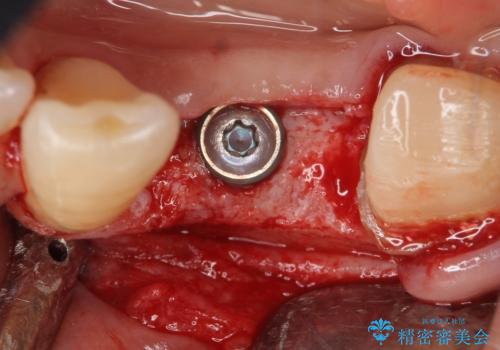

- 左下の歯並びが悪く、左側で物が咬みにくいので診て欲しいといらっしゃった方の症例です。

歯列矯正は御希望されなかったため左下4、5番目の歯を抜歯し、インプラントによる欠損補綴を行いました。

当院では主にストローマンという種類のインプラントを治療に用いています。

ストローマンは世界的にもNo1のシェアを誇り、骨との適合にも優れたインプラントです。